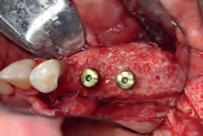

tiële wortelkanaalbehandeling uitgevoerd. Na het lokaliseren van de twee distale en de twee mesiale kanalen, viel het op dat in het mesiolinguale kanaal een restant pulpaweefsel bleef ‘hangen’ nadat het element zorgvuldig was gespoeld. Verdere exploratie leerde dat hier sprake was van een mid-mesiaal wortelkanaal. In totaal werden in deze casus dus 5 wortelkanalen gevonden!

Afbeelding 2. Het plan was om een pulpotomie te doen. Bij het openen van de pulpakamer, kwam er wat pus ophoog. Omdat de aanwezigheid van pus een contra-indicatie is voor een pulpotomie, werd besloten om een initiële wortelkanaalbehandeling uit te voeren.

Afbeelding 3. De mesiale kanalen lijken wel een vitale pulpa te hebben, deze bloedt bij het openen.

Afbeelding 4. Het viel op dat in het mesiolinguale kanaal een restant pulpaweefsel bleef ‘hangen’ nadat het element zorgvuldig was gespoeld. Verdere exploratie leerde dat er hier sprake was van een mid-mesiaal wortelkanaal. Op de foto is fraai te zien dat het echt om twee aparte kanalen gaat.

Afbeelding 5. In totaal worden er in dit gebitselement dus 5 wortelkanalen gevonden. Waarschijnlijk zijn er nog talloze anastomoses, maar die moeten we schoonkrijgen door een goed spoelprotocol.